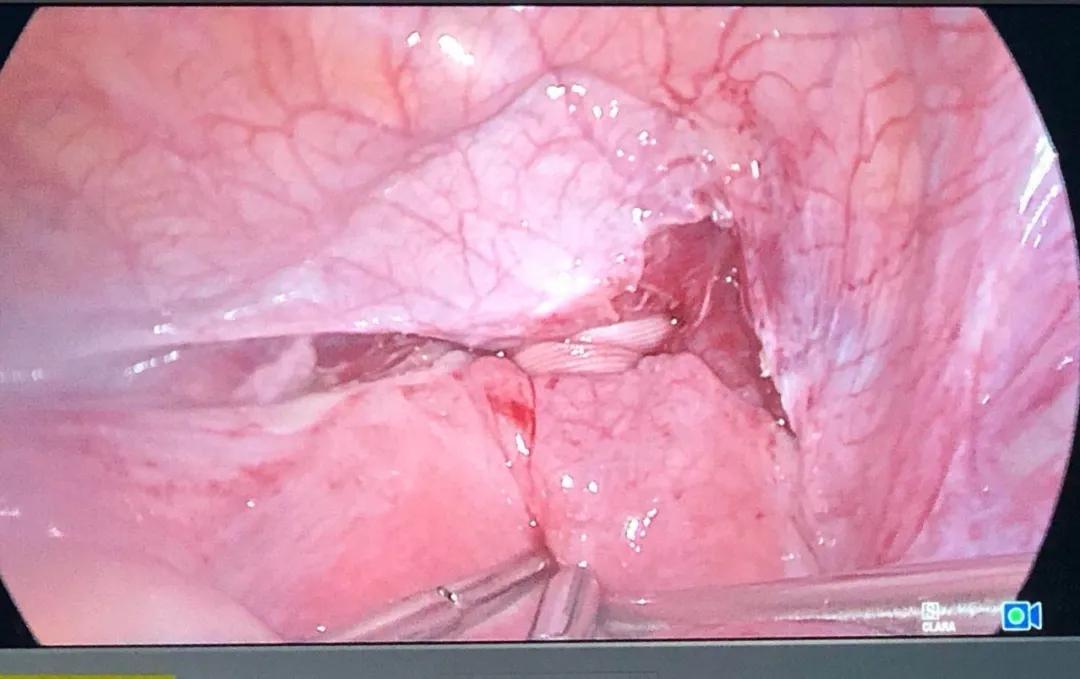

在子宫峡部、血管内侧,将慕丝林环扎带的穿刺针直接由前向后穿过,排除慕丝林环扎带位于宫颈管内,最后将慕丝林环扎带打结4~5个结,完成宫峡部环扎术。